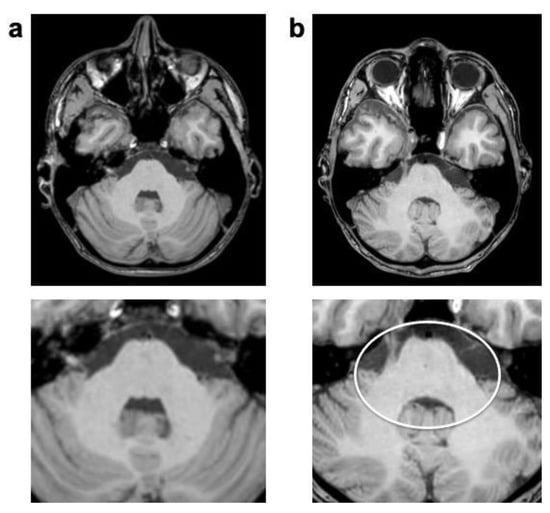

The CS FLAIR benefited mostly from a reduction in physiological artifacts (overall p < 0.001), namely, an improved suppression of cerebro-spinal fluid flow artifacts (p < 0.001) and elimination of the dependent ghosting artifacts (p < 0.001; see Figure 6). CS FLAIR was the only sequence to demonstrate a significant decrease in motion artifacts (p = 0.005) caused by head or eye movement. However, CS FLAIR images were deemed slightly noisier than standard images on visual inspection.

Figure 6.

FLAIR images of a 5-year-old male patient with astrocytoma (post-resection). Bright CSF-flow-related enhancement (FRE, arrowheads) in fourth ventricle and prepontine cisterns is seen in SENSE FLAIR (a), not present in CS FLAIR (b). As a consequence, the CSF-dependent ghosting artifacts (arrow) did not occur.